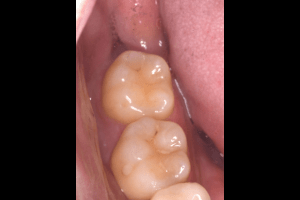

親知らずが虫歯になっている症例

- 抜歯前の口腔内写真

| 主訴 | 主訴:親知らずを抜きたい 治療部位:左下の親知らず |

| 親知らずの生え方 | 斜めに生えている |

| 抜歯時間 | 説明、麻酔等含めて約60分 |

| 抜歯内容 | 左下8番の普通抜歯 |

| 治療方針 | 初診時に親知らずの虫歯を確認しました。 先に別の部位の治療をしていましたが、痛みが出てきたため抜歯を行うこととなりました。 |

| 特記事項 | 抜歯をする前にCTを撮影をし、下歯槽神経との位置を確認した上で抜歯を行いました。 |

| 担当者所見 | 初診のご来院時から、すでに虫歯が大きく進行していました。 ご来院時にお痛みはなかったものの、大きい虫歯でしたので、いつ痛みだしてもおかしくない状態でした。 麻酔が効きづらかったため抜歯に時間を要しましたが、根が折れることなく無事に抜けました。 |